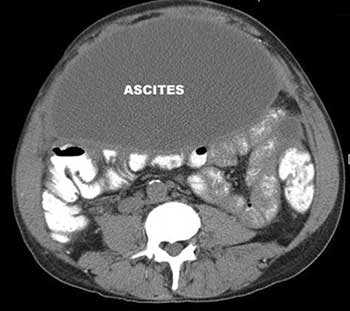

Асцит — патологическое состояние, при котором в брюшной полости скапливается жидкость. Причины его бывают различными. Чаще всего к асциту приводит цирроз печени. Так же он возникает как осложнение онкологических заболеваний, при этом ухудшается состояние больного, снижается эффективность лечения.

Если в брюшной полости скапливается небольшое количество жидкости (100-400 мл), симптомы отсутствуют. В таких случаях асцит обнаруживают зачастую случайно во время УЗИ или КТ органов брюшной полости.

Внешние признаки асцита становятся хорошо заметны, когда количество жидкости в брюшной полости достигает 0,5-1 литра. Живот при этом заметно увеличен. Когда пациент стоит, он выглядит отвисшим, в положении лежа — распластан, боковые его части выступают. Врачи называют такую картину образно «животом лягушки».